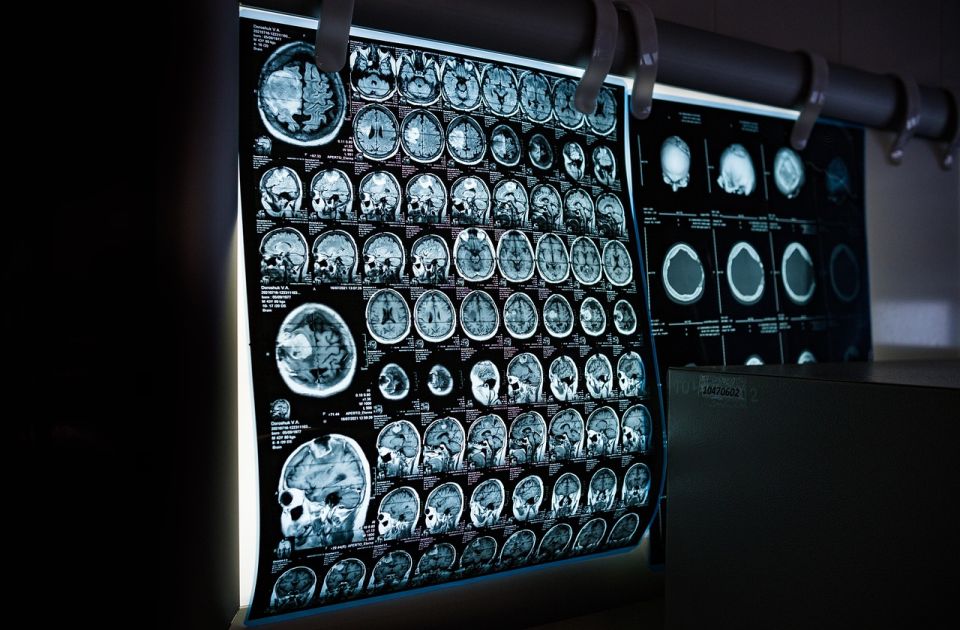

Foto: Pixabay

Dr Bearer je u svom radu o ulozi vaskularnih faktora u nastanku kognitivnih poremećaja analizirala više prethodnih studija kao i mikroskopske snimke moždanog tkiva ljudi koji su preminuli sa dijagnozom demencije.

Njena analiza pokazala je da mozak ovih osoba sadrži znatno više mikroplastike nego mozak ljudi bez kognitivnih poremećaja. Ta zapažanja otvaraju nova pitanja o tome kako zagađenje plastikom može uticati na funkcionisanje ljudskog mozga.